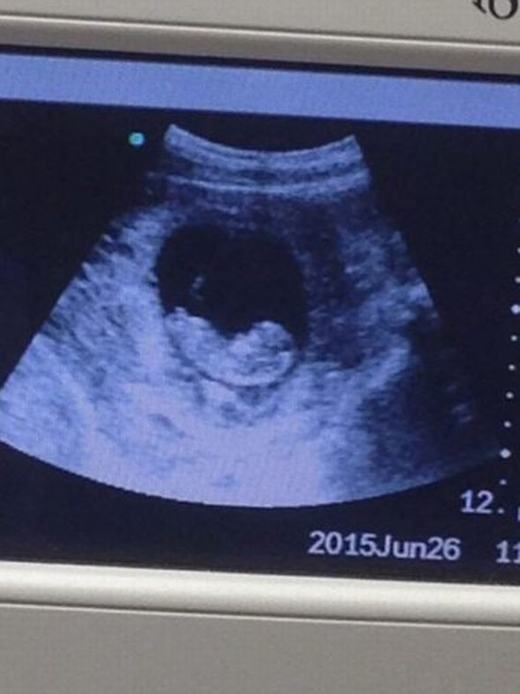

Mới đây, hình ảnh siêu âm thai của một người phụ nữ đã khiến cộng đồng mạng hoang mang tột độ. Cụ thể là trên bức ảnh đó bất ngờ xuất hiện hình ảnh giống như của “quỷ dữ” bên cạnh bào thai. Từ lúc bức ảnh được đăng tải trên mạng đã có rất nhiều luồng ý kiến trái chiều về hình ảnh của “quỷ” đó.

Thông thường, khi siêu âm người ta chỉ nhìn thấy em bé. Tuy nhiên mới đây, hình ảnh “quỷ dữ” xuất hiện trên màn hình bên cạnh thai nhi làm cho mọi người không khỏi giật mình. Nếu nhìn lướt qua, có thể nhiều người nghĩ đây là một bức ảnh siêu âm bình thường như bao ảnh siêu âm khác.

Theo tờ báo nổi tiếng của Anh Express mô tả, hình ảnh siêu âm có thể bình thường khi mới nhìn vào với thai nhi trong bào thai. Nhưng nếu quan sát kĩ hơn, nhất là ở góc phải, ta sẽ thấy hình ảnh của một người khác với khuôn mặt dữ tợn đang nhìn vào thai nhi.

Cái này mới là quỷ đỏ hình gốc nè ,tin từ báo mang tiếng quân hại nhân dân chụp tại xưởng đẻ Từ Dũ :